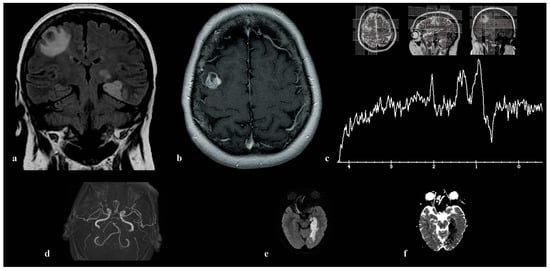

3.1. Patient 1